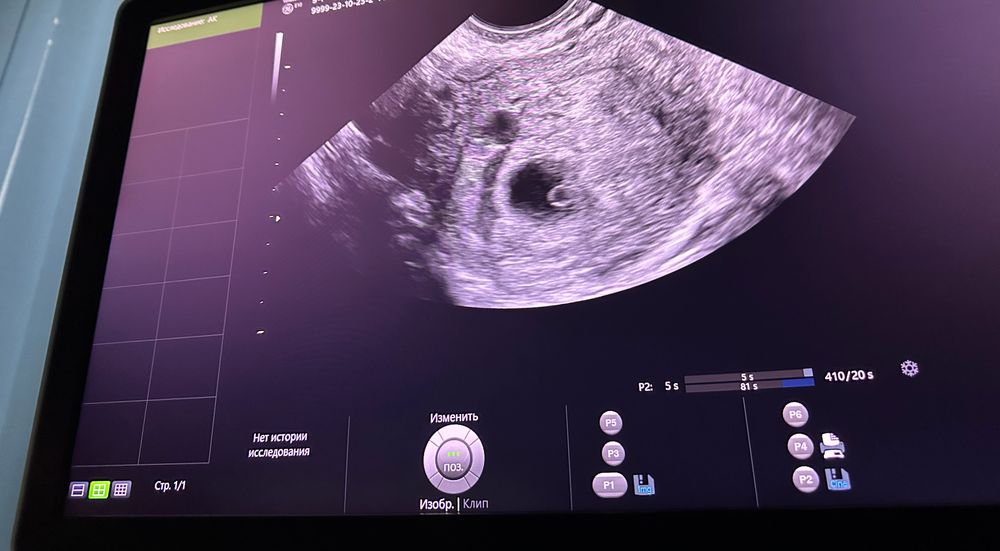

Первое УЗИ малыша 🥰

Изображение УЗИ первое Акушерский да) она сказала только все ок))) дала послушать сердце

Поздравляю! Какой ктр не сказали? 😍

Мария, 0,54 см написано)